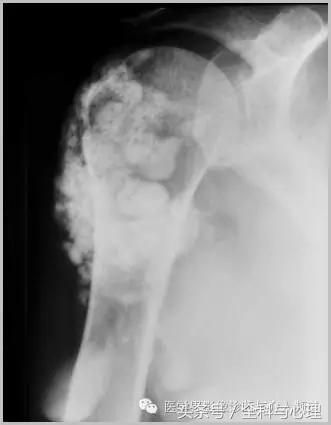

五、滑膜软骨瘤病

1°少见,病灶数量多,大小均匀,相邻关节正常。

2°多见,病灶数量少,大小不一,多伴有退行性骨关节病。

软组织钙化与骨化,软组织钙化和骨质增生 滑膜骨软骨瘤病 1°

软组织钙化与骨化,软组织钙化和骨质增生 滑膜骨软骨瘤病 2°

软组织钙化与骨化,软组织钙化和骨质增生 滑膜骨软骨瘤病